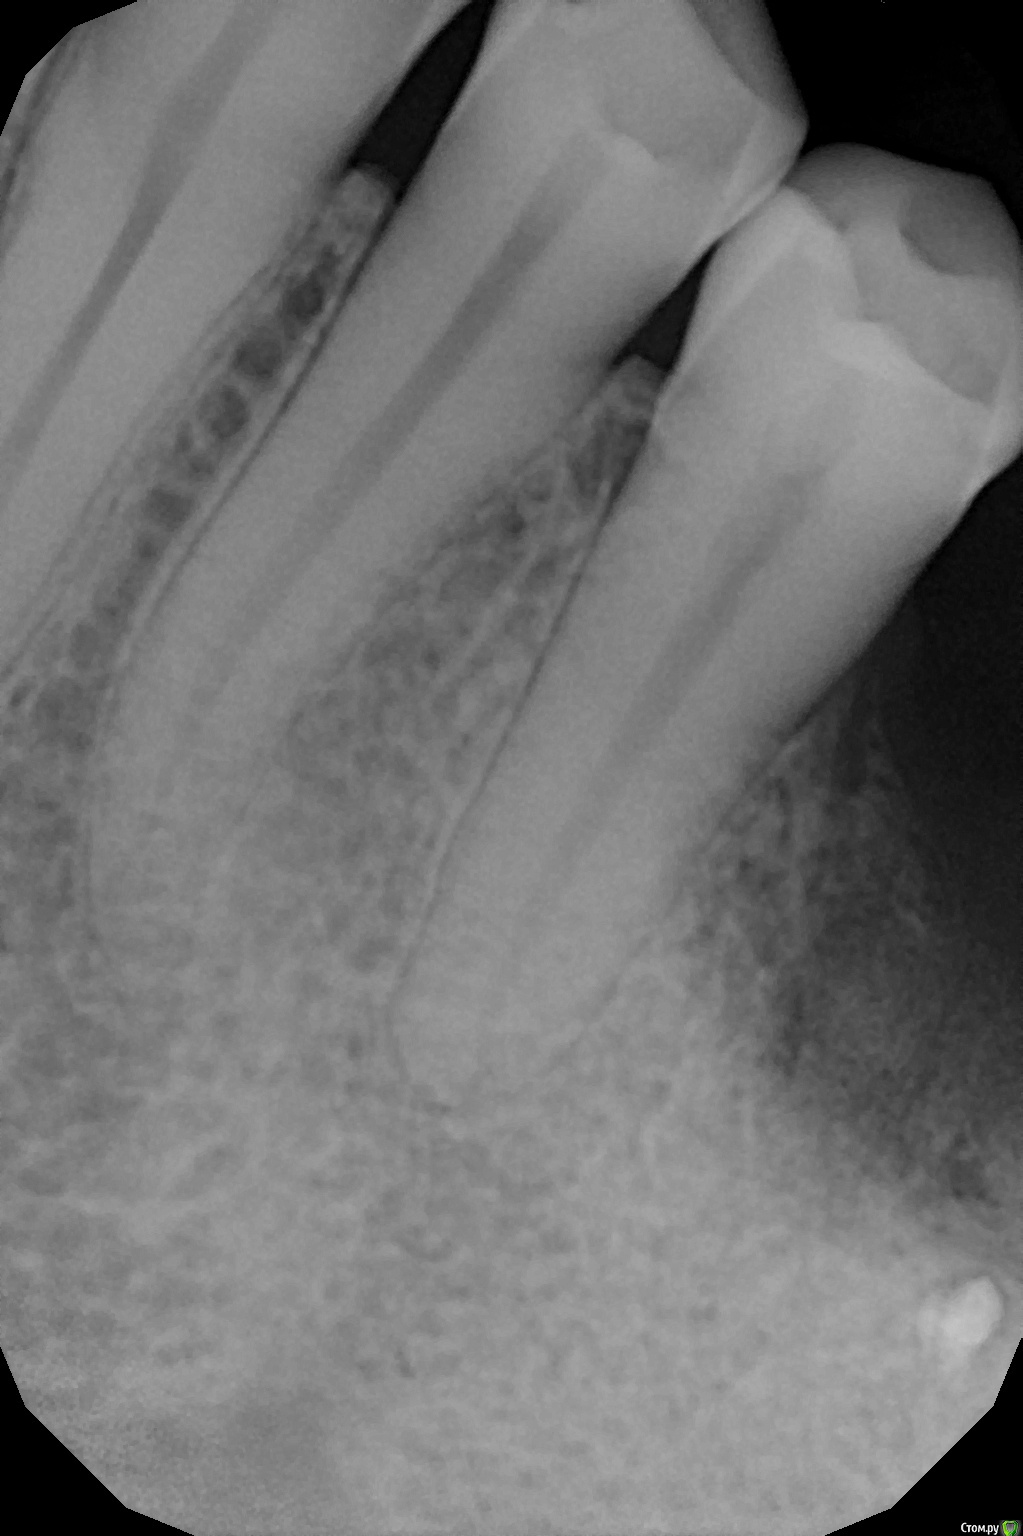

Xael Опубликовано 7 ноября, 2017 Автор Поделиться Опубликовано 7 ноября, 2017 (изменено) Добавляю рентген-фото больного зуба 3.4: Добавляю также фото больной(?) десны: Изменено 7 ноября, 2017 пользователем Xael Ссылка на комментарий

red_butler Опубликовано 7 ноября, 2017 Поделиться Опубликовано 7 ноября, 2017 снимок не информативен, верхушка корня не видна.Нужны термо проба хладагентом и/или ЭОД Ссылка на комментарий

Xael Опубликовано 7 ноября, 2017 Автор Поделиться Опубликовано 7 ноября, 2017 снимок не информативен, верхушка корня не видна.Нужны термо проба хладагентом и/или ЭОД Переделал снимок, термо и ЭОД только завтра возможны Ссылка на комментарий